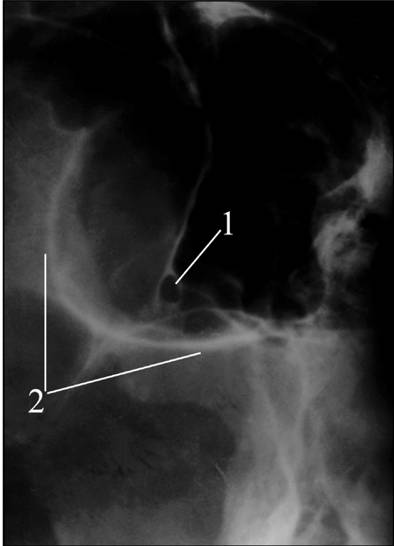

Рентгенография глазницы в передней косой

проекции (снимок зрительного канала по Резе)

Основное назначение снимка - получение

изображения зрительного канала. Снимки для сравнения производятся обязательно с

обеих сторон.

На снимках отображаются зрительный канал, вход в

глазницу, решетчатые ячейки (рис.2).

Рис. 2. Рентгенограмма глазниц в косой плоскости

по Резе. Норма